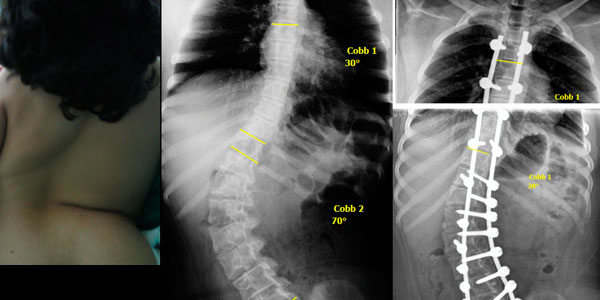

Paciente de 1 año y 8 meses con escoliosis congénita progresiva, se realizo resección de hemivertebra con colocación de tornillos transpediculares.